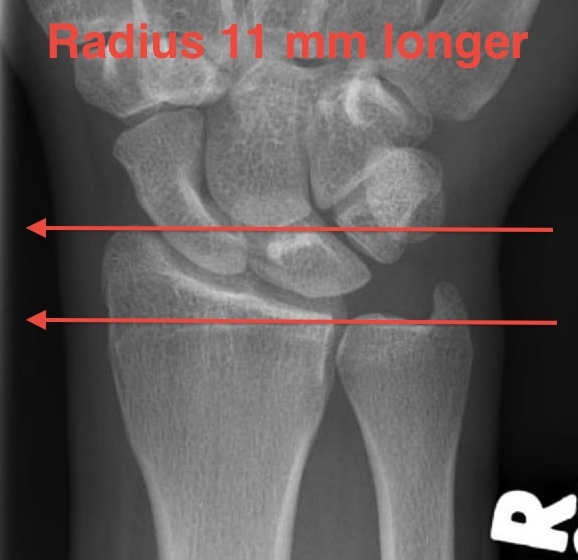

Distal Radius Angles

- radius is 11 mm longer than ulna

- ulna variance 2mm positive on average